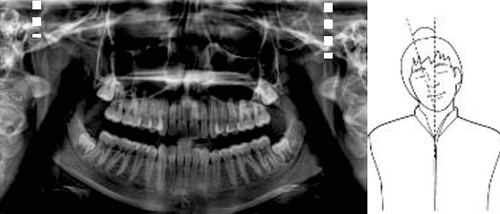

●正中線のずれ

左右非対称→顔が傾いている